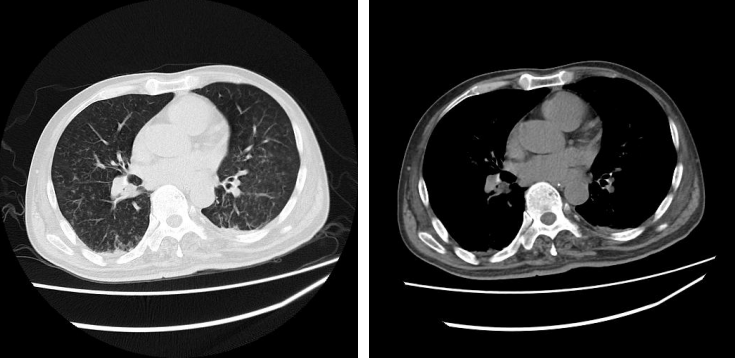

治疗效果

治疗1周后,于11月15日复查胸部CT示:双肺渗出实变较前明显好转,心包少量积液,双侧少量胸腔积液,双肺不张较前明显好转。

图片